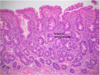

Normal Small Intestine

Normal Colon